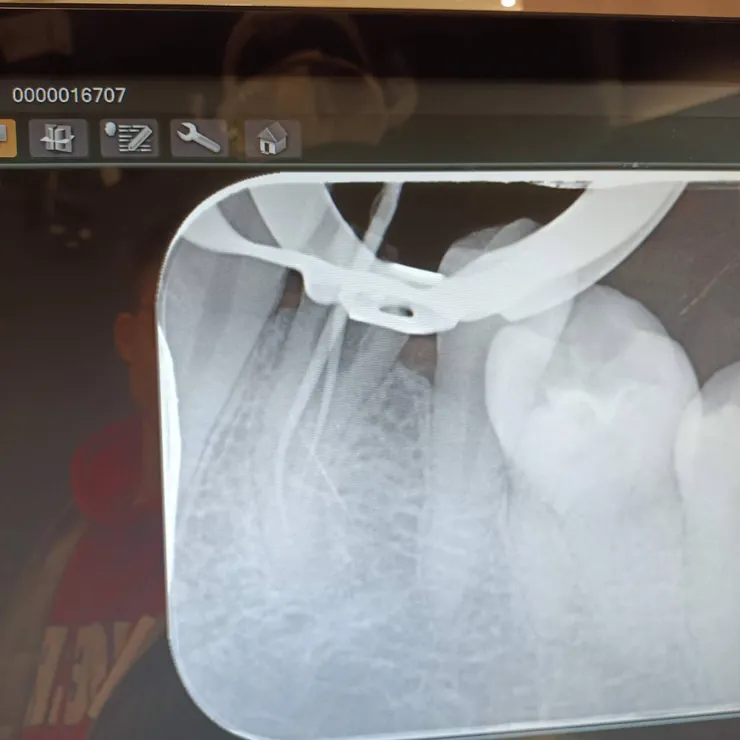

兩根根管的樣子

根管被填起來的樣子